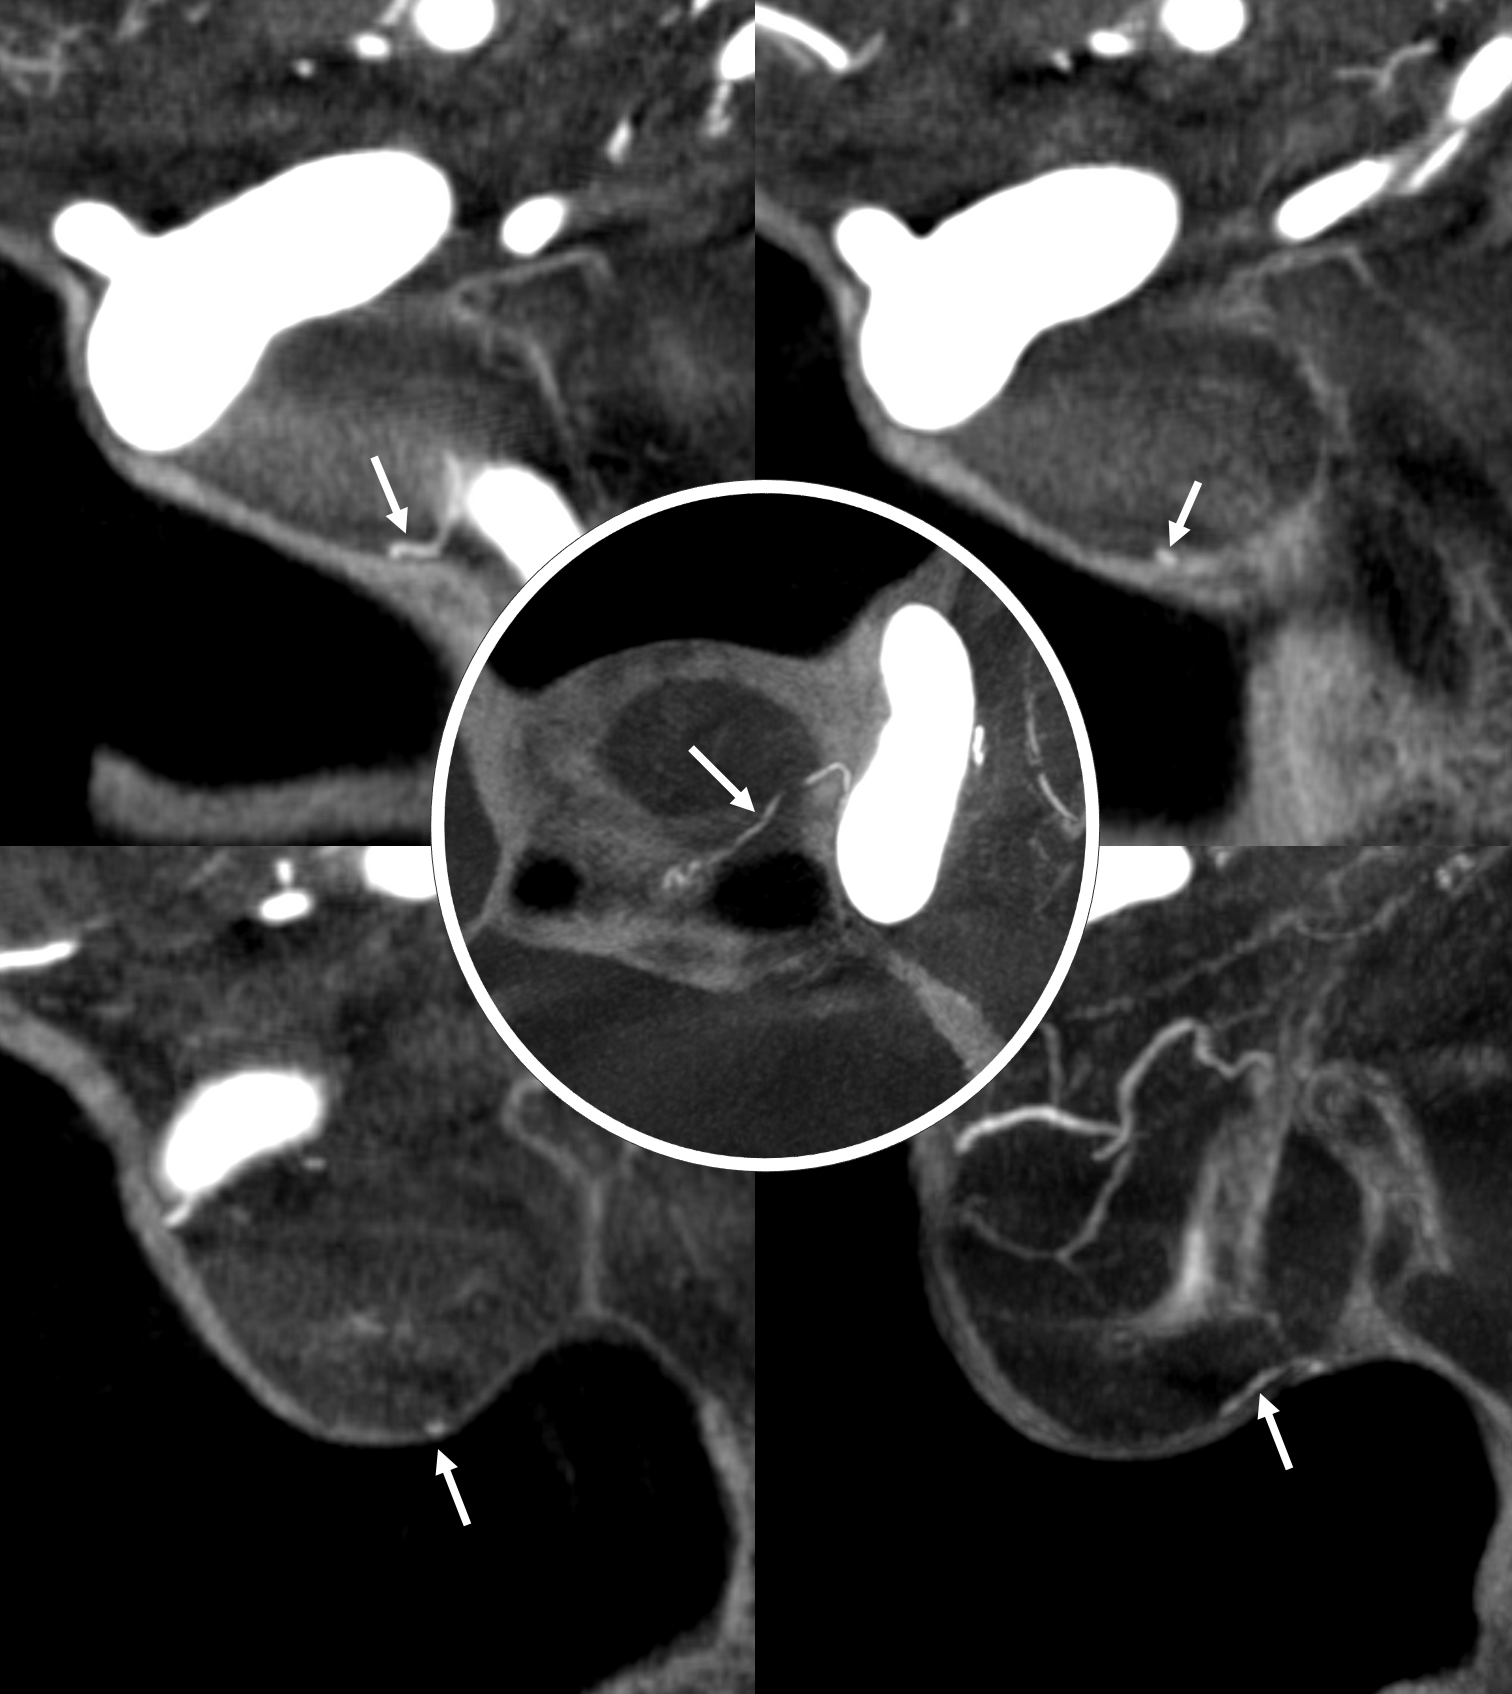

Capsular Arteries of McConnell

These are different from Superior Hypophyseals, but often come up together. This is because they were described by McConnell in a fantastic manuscript on arterial supply to the hypophysis. The anterior hypophysis is supplied by the aforementioned superior hypophyseals. Posterior by the inferior hypophyseals. The arteries of McConnell supply the dura and bone of the sella turcica. They are considered dural, and do not as a rule supply the hypophysis. Too small for even HR CBCT resolution, they are found in about 1/3 to 1/2 of surgical dissections. Origin is from the MEDIAL aspect of the horizontal cavernous segment (opposite side of ILT). Courses medially towards the bottom of the sella. Below (arrows) is a particularly large one (because it feeds some posterior pituitary for some reason). Note beautiful anterior pituitary / stalk supply on bottom right image.

Without arrows: